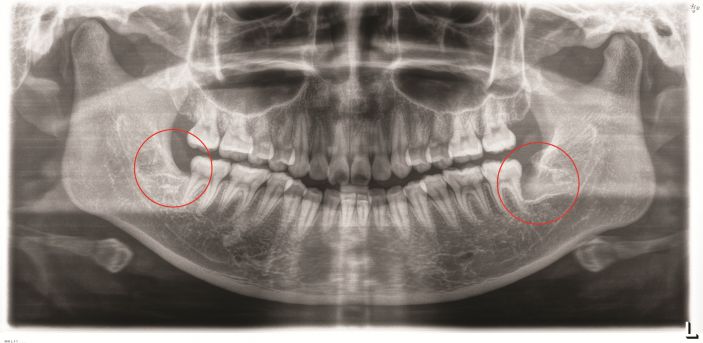

△智牙拔除前。

△智牙拔除後。